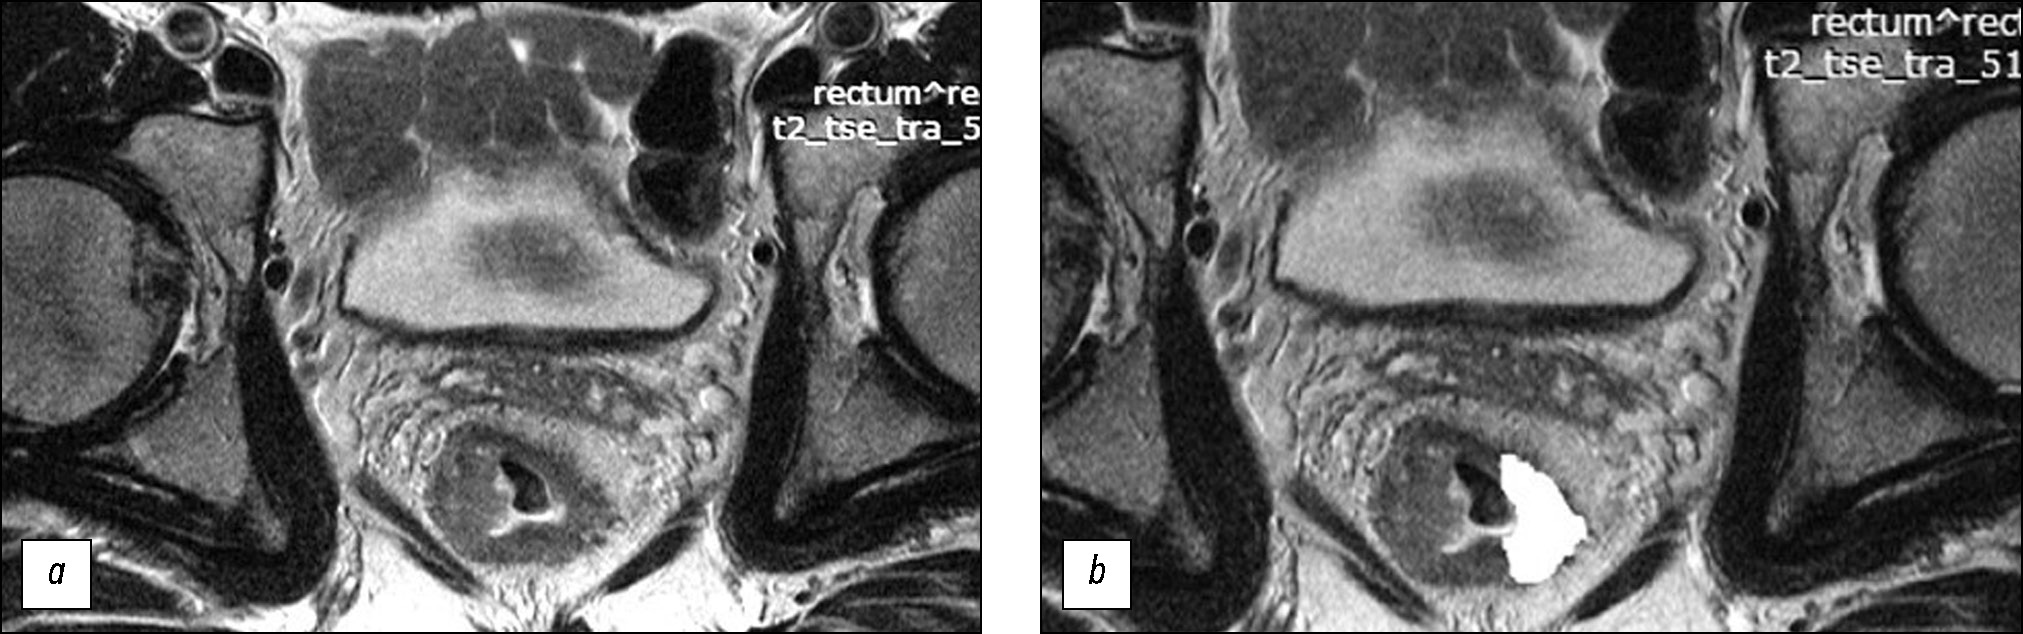

AIM: To assess the texture characteristics of locally advanced rectal cancer in primary T2-weighted imaging (T2-WI) as a potential predictor for the efficacy of standard neoadjuvant chemoradiotherapy and develop a prediction system for the efficacy of neoadjuvant chemoradiotherapy based on them.

MATERIALS AND METHODS: The retrospective study enrolled 82 patients with locally advanced rectal cancer who received combination treatment with neoadjuvant chemoradiotherapy. Patient data were divided into the training (n=58) and control (n=24) sets. For texture analysis, primary high-resolution T2-WI at the level of the tumor center, oriented perpendicular to the intestinal wall, was used. The texture analysis was performed by second-order statistics based on the gray-level co-occurrence matrices using MAZDA ver. 4.6 featuring the calculation of 11 texture parameters. In the training set, based on the morphological assessment of surgical specimens, significantly different texture analysis parameters were found for two groups of patients: neoadjuvant chemoradiotherapy responders (good prognosis group) and nonresponders (poor prognosis group). Accordingly, a scoring system was created for assessing the efficacy of neoadjuvant chemoradiotherapy. The system was tested on the control set, and diagnostic efficacy parameters were determined.